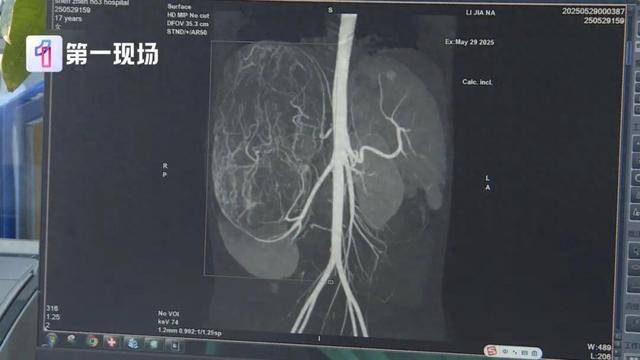

等到了当地医院一检查,CT结果显示,她的右肾有恶性肿瘤伴肝转移可能,家长就立即带着孩子来到深圳求医皇冠信用網在线申请 。

肿瘤已经到了肚脐的下缘,就是后腹直肌外侧,这种情况需安全地把肿瘤切除,不要把肿瘤搞破,是我们首先要考虑的问题皇冠信用網在线申请 。

切除的肿瘤将近5斤重

直径达27厘米

肿瘤切出来后,我们测量了大小有27公分,重量有2.435公斤,非常非常的大皇冠信用網在线申请 。